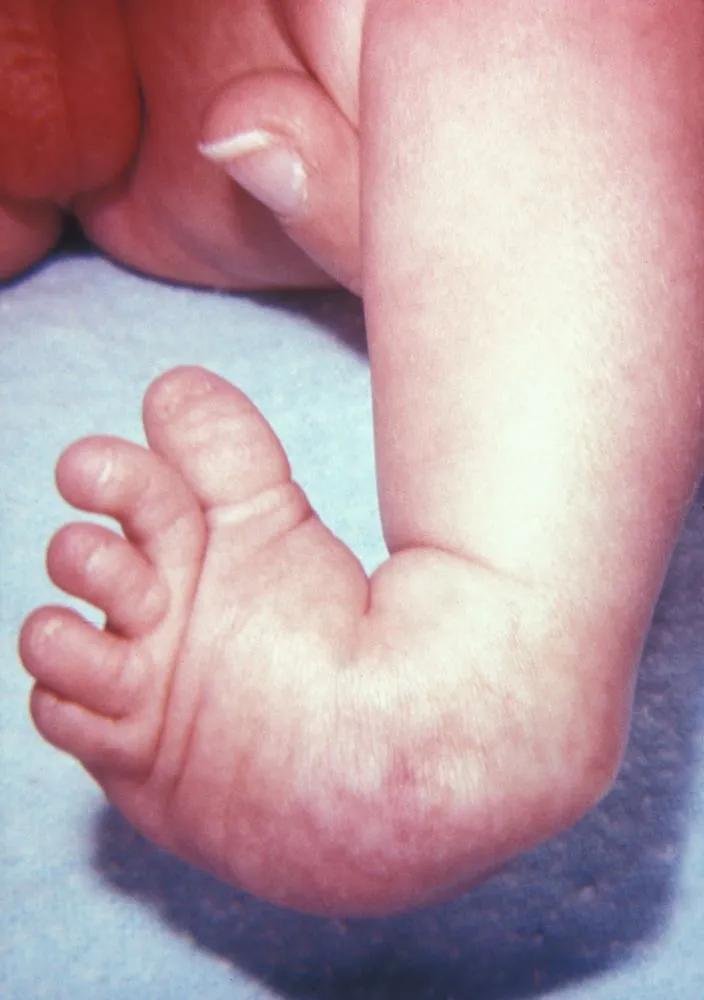

这是一个刚满月的宝宝,摆在医生面前的就这三样东西:一张胸部X光片、一张足部外观照、还有一张血常规化验单。

症状很明显但很分散,就像几个不相干的毛病,这就很考验模型捕捉碎片信息和综合分析的能力。

但WiseDiag V2并没有盲人摸象,而是整体思考:

在足部外观照中精准识别了足部的马蹄内翻;

综合所有信息给出正确的诊断结果——VACTERL联合征。

VACTERL联合征是一种罕见的非随机先天性多系统发育畸形组合,通常由至少三种特定器官缺陷组成:脊柱畸形(V)、肛门闭锁(A)、心脏缺陷(C)、气管食管瘘/食管闭锁(TE)、肾脏畸形(R)和肢体异常(L)

由此可见,WiseDiag V2是一个医疗AI强大的多模态认知底座。